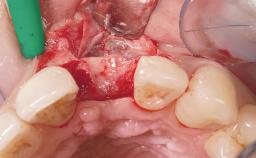

A 30-year-old female patient was referred to the office for the treatment of tooth 11. Her chief concern at the initial visit was to inquire, “Why is my tooth pink?” Upon clinical examination, it was determined that tooth 11 had a previous history of trauma and that the clinical crown had become noticeably pink in color as a result of internal resorption. This diagnosis was confirmed radiographically, indicating a large radiolucency involving the central and distal portions of the clinical crown. It was determined that restoration of this tooth was not possible, and that extraction was indicated. The presence of a mid-line diastema, which the patient wanted to reproduce, directed the treatment plan for tooth replacement utilizing a dental implant.

Placement Protocol Immediate implant placement

Socket Morphology Single-root socket

Socket Integrity Sufficient, with intact bone walls